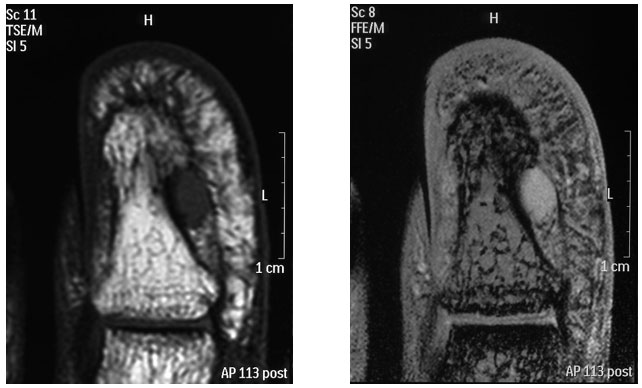

A. 局所(圧痛や寒冷刺激)所見や、画像ではエコーやMRI等で2㎜程度のものであれば、描出可能です3)。

MRI(左T1:低輝度、右T2:高輝度)